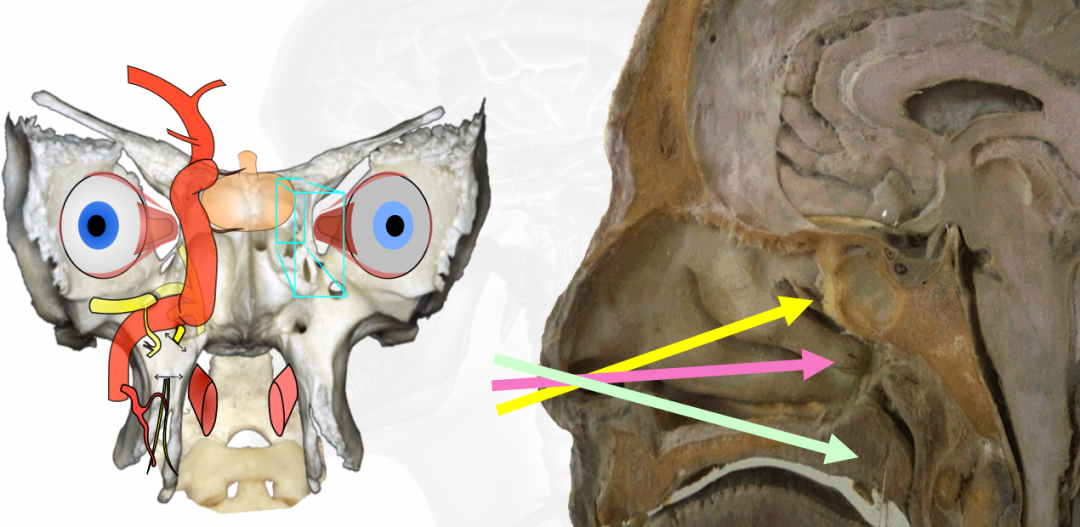

▼单鼻孔经鼻内镜手术操作示意图

使用“筷子技术”神经内镜手术,从右侧蝶窦水平到鼻后孔垂直切开鼻腔粘膜,部分分离鼻腔粘膜,打开蝶窦。

内镜经鼻入路具有显著的入路相关的发病率,保持过去经常被低估的鼻腔生活质量是颅底神经外科医生的下一个挑战,即使全切除仍然必须是脊索瘤手术的主要目标。为了提高生活质量,近年来,除了有针对性的入路外,我们更倾向于单鼻孔“筷子技术”,用于中线脊索瘤,允许外科医生在狭窄的通道内工作,并减少与入路和血管化鼻中隔皮瓣相关的发病率。